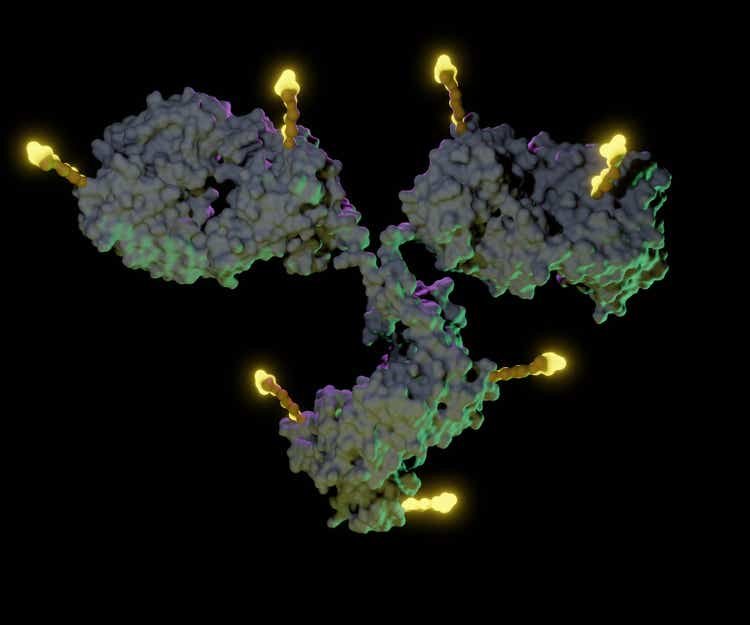

Seagen focuses on antibody-drug conjugates (ADCs), a technology that the company says can “harness the targeting power of antibodies to deliver small molecule drugs to the tumor.”

The good news for Pfizer (PFE) is that GlobalData sees the Seagen (SGEN) acquisition as a good fit. “What’s most impressive…is Seagen’s (SGEN) ability to develop a wide range of monoclonal antibodies, that target different cancer types,” says GlobalData Oncology & Hematology Analyst Israel Stern. “This capacity will now be enhanced by leveraging Pfizer’s (PFE) protein engineering capabilities.”